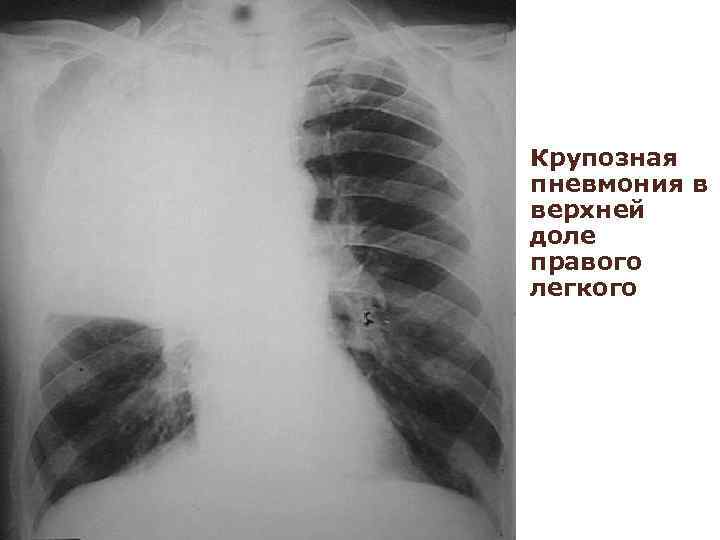

Рентген легких: диагностика и современные технологии